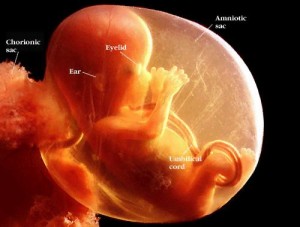

18 haftalık bebek Bebeğinizin göz kapakları halen kapalı olmasına rağmen karanlık ve ışığı ayırt edebiliyor.

Parmak izleri oluştu bile! Bebeğiniz cinsiyetini hala öğrenemediyseniz belki de bu hafta öğrenebilirsiniz.